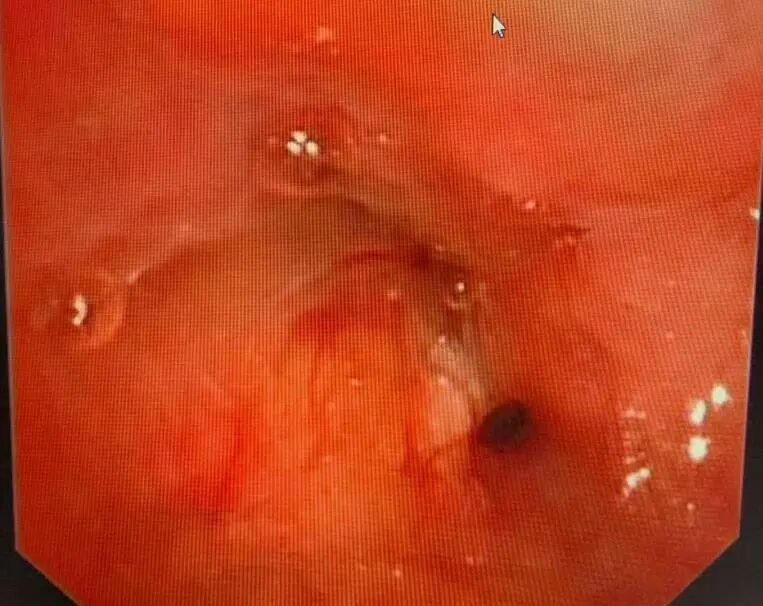

进一步的病理诊断结果明确:王叔患上的是鳞状细胞癌。气管镜检查下,能清晰看到左侧支气管管口被新生物堵塞,肿瘤牢牢“盘踞”在左上肺根部。如果贸然开刀,不仅要切除整个左肺,甚至可能因为肿瘤与血管、支气管粘连过紧,无法实现根治性切除,反而会给患者带来更大的创伤。

1-1.jpg

支气管镜下可见左上叶支气管口新生物